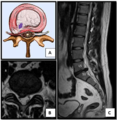

Lumbar disc lesions, classification

Normal situation and spinal disc herniation in cervical vertebrae.

Illustration depicting herniated disc and spinal nerve compression

Nucleus herniating through tear in anulus (with MRI)[1]